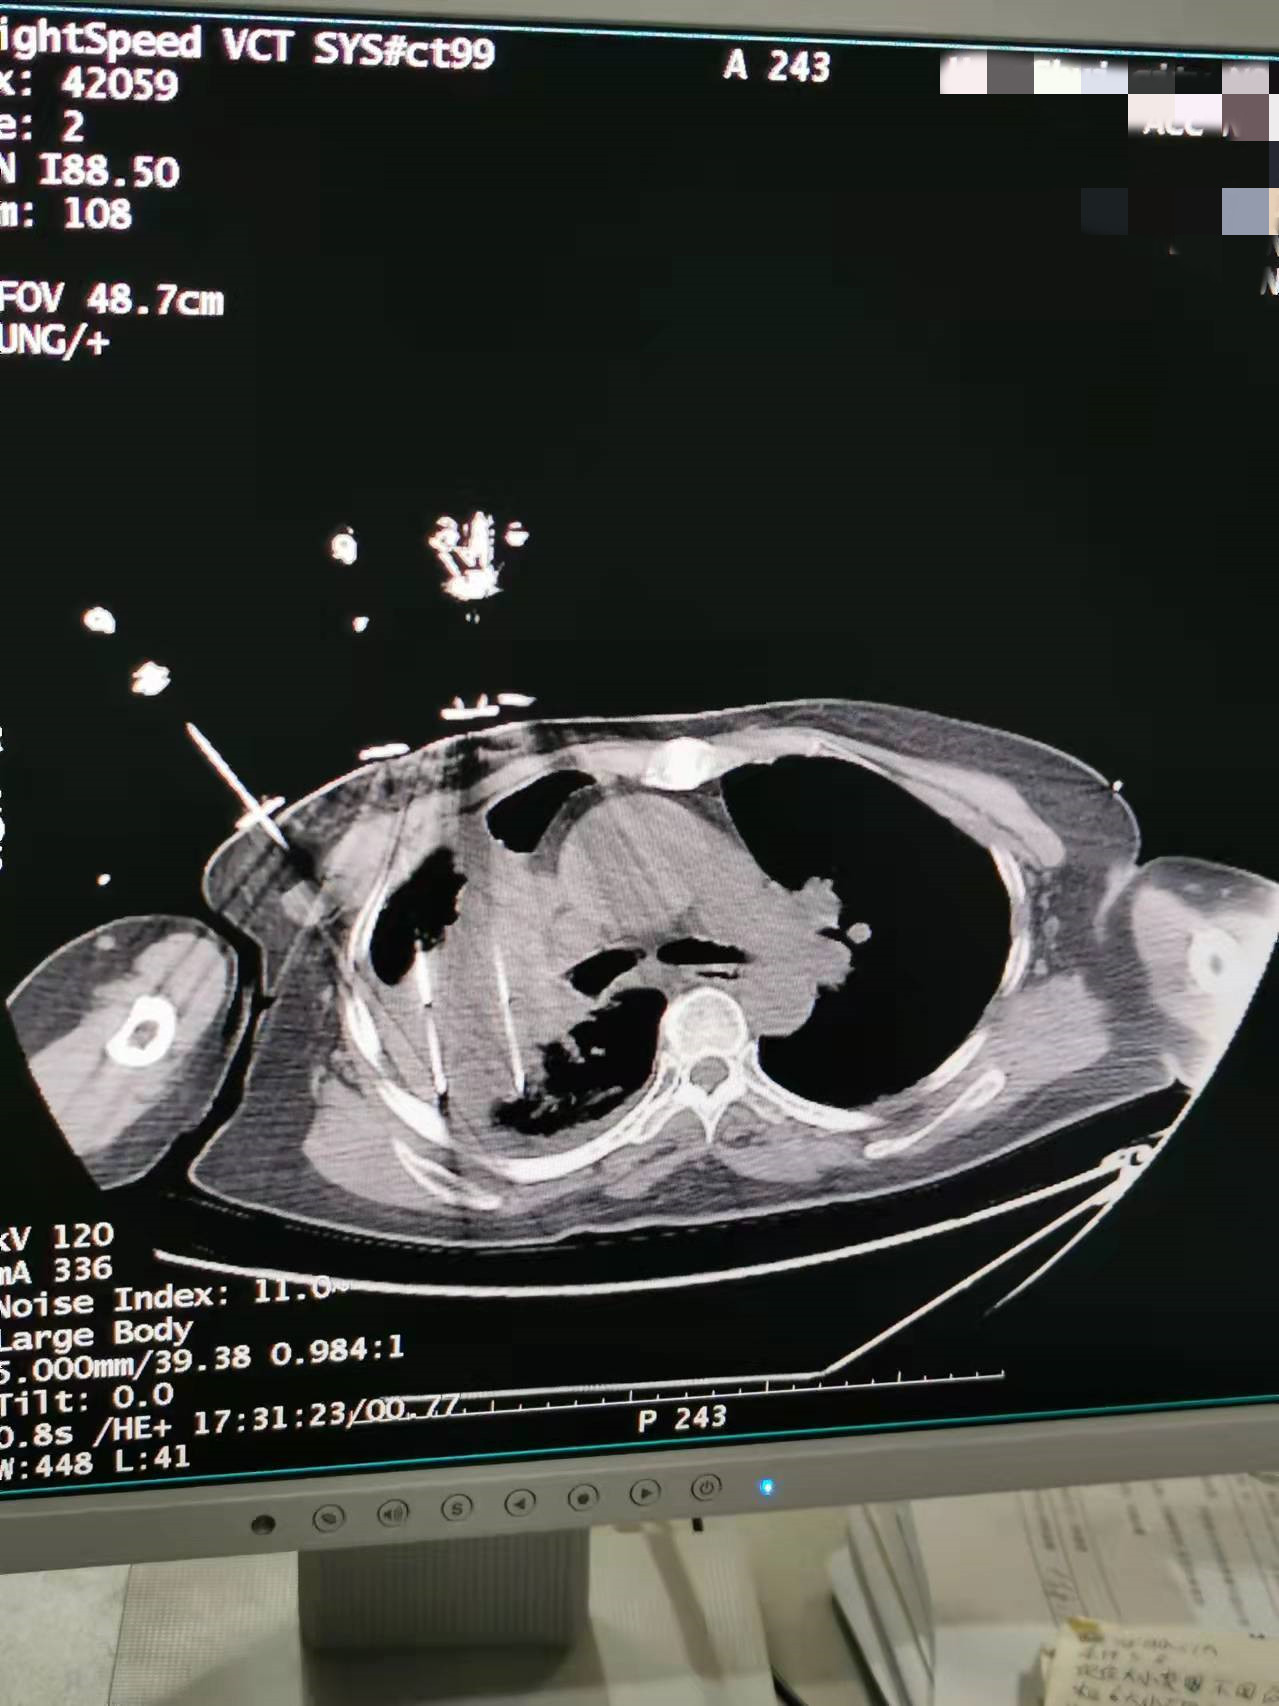

2021年11月份肺部氩氦刀手术

发布人:美国氩氦刀技术官方网站    发布时间:2021/11/26 14:02:23